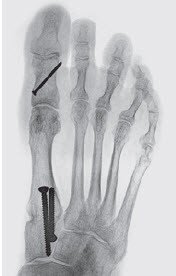

Ziel der Chirurgie ist die möglichst exakte Wiederherstellung einer normalen Anatomie, wie sie vor dem Auftreten der Deformität bestanden hat. Der schräg stehende Mittelfussknochen, der nach innen drückt, muss also aufgerichtet und in der korrekten Stellung stabilisiert werden. Die Grosszehe steht dann wieder gerade auf dem Mittelfussknochen und entfaltet ihre volle Stützfunktion, was die Überlastungsschmerzen an der Fusssohle zum Verschwinden bringt. Das bei uns am häufigsten angewandte Operationsverfahren ist die sogenannte «Scarf»-Osteotomie, die hier dargestellt wird. Diese Korrektur erfolgt durch einen Knochenschnitt (Osteotomie), der mit zwei bis drei kleinen Schrauben in der korrekten Stellung bis zur Heilung (sechs bis acht Wochen) fixiert wird. Die später funktionslos gewordenen Schrauben spürt man nicht, sie müssen nur ausnahmsweise entfernt werden.

Diese Operation, die ohne Weiteres in alleiniger Betäubung des Fusses durchgeführt werden kann, dauert in der Regel weniger als eine Stunde. Auch wenn Komplikationen nie ganz ausgeschlossen werden können, sind sie bei der Hallux-valgus-Chirurgie selten und so gut wie nie schwerwiegend.